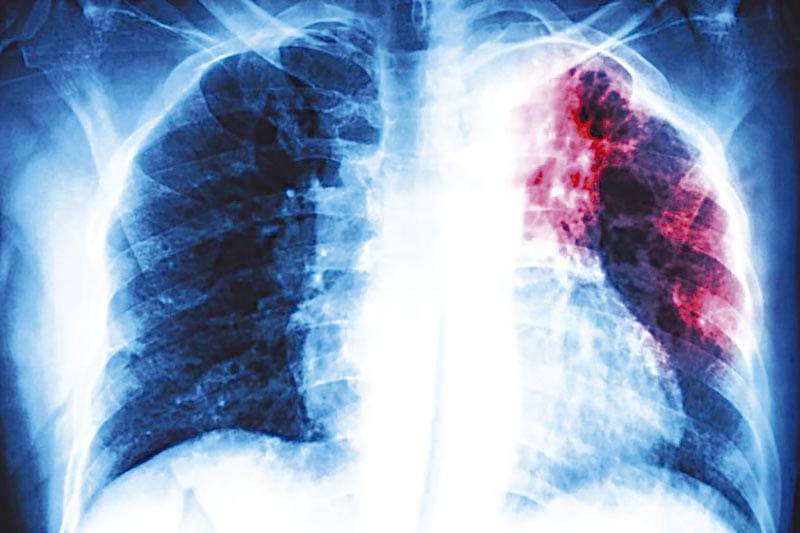

Xalapa, Ver.- El estado de Veracruz es primer lugar a nivel nacional en cuanto a casos detectados de tuberculosis respiratoria con 434 pacientes diagnosticados en lo que va de este 2025.

La Secretaría de Salud federal, a través del Sistema de Vigilancia Epidemiológica reporta que se han reportado 280 casos en hombres y 154 entre mujeres.

Con esa cifra la entidad se ubica en el primer lugar a nivel nacional en cuanto a casos de esta enfermedad.

Por detrás del estado de Veracruz se encuentra Nuevo León con 424 casos, Baja California con 417 casos diagnosticados, Sinaloa con 328.

En la lista también aparece Tamaulipas con 315, Chiapas con 310, Sonora con 284, Jalisco con 206, entre otras.